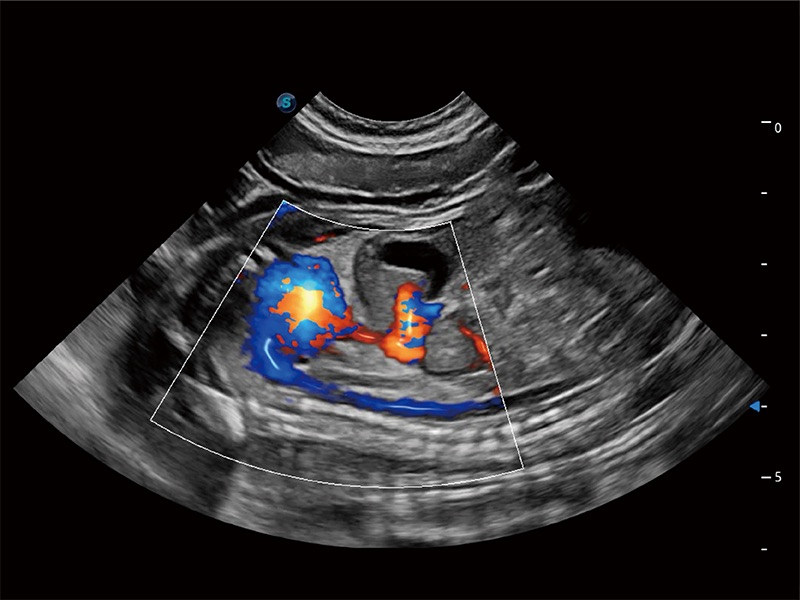

高性能和先进的临床应用工具可以为动物医生提供临床信心。ProPet 80 搭载了先进的腹部和浅表应用工具,帮助医生在日常临床实践中发挥前所未有的作用。

极大提升超低速微细血流的检出能力,同时更精准地滤除软组织和超声信号,为兽用医生提供以往无法通过常规血流获得的疾病诊断信息。